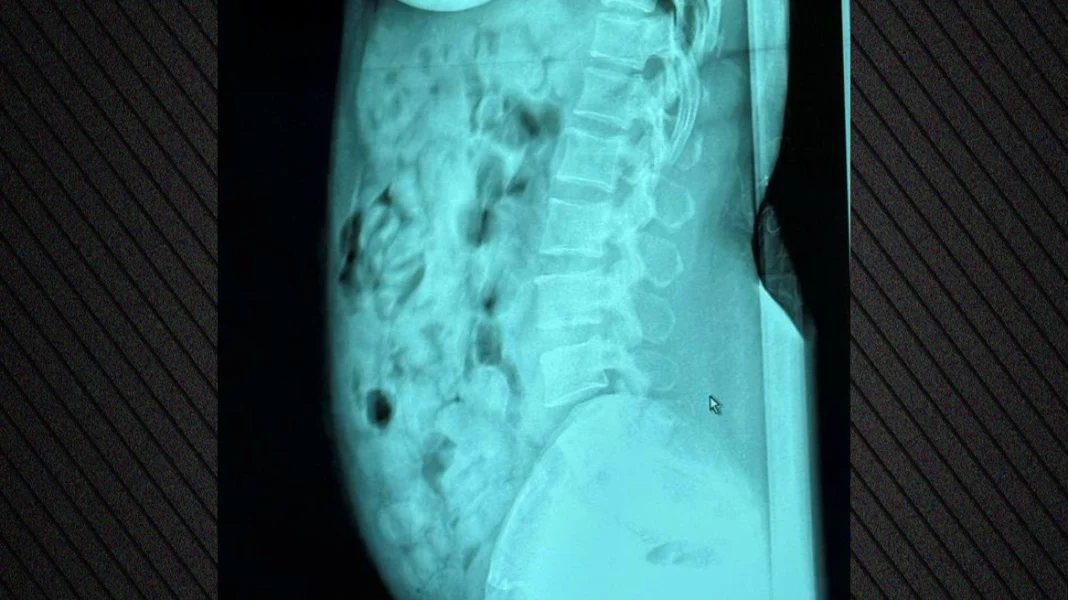

Ακτινολογικές εξετάσεις στο νοσοκομείο του Μπέργκαμο επιβεβαίωσαν την παρουσία ναρκωτικών, τα οποία ήταν σφραγισμένα με κολλητική ταινία. Μετά την αποβολή τους, η ουσία κατασχέθηκε και η γυναίκα οδηγήθηκε στη φυλακή του Μπέργκαμο, στη διάθεση της δικαστικής αρχής.

Δείτε φωτογραφία: